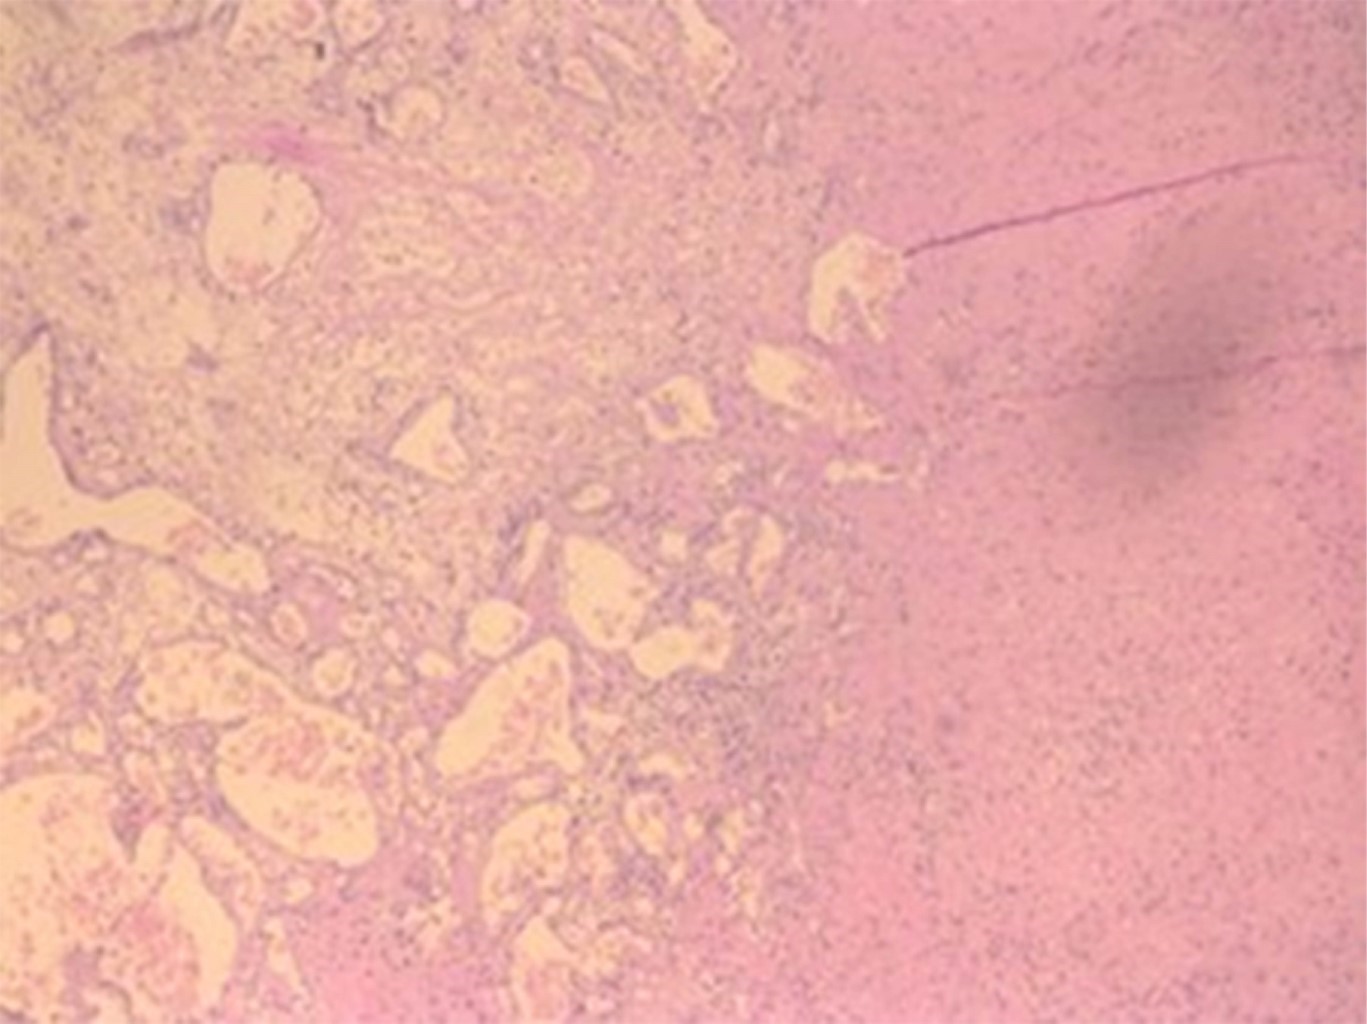

Histológicamente, estas lesiones muestran canales vasculares displásicos sin mitosis activa, diferenciándose de los hemangiomas verdaderos. Además, se ha demostrado un ambiente proangiogénico con expresión aumentada de VEGF, Ang-2, HIF-1α y TIE2, lo que favorece la fragilidad capilar y el sangrado.5,6

Se realiza biopsia incisional de lesión adyacente al diente 4.8 y unas semanas más tarde se confirma el diagnóstico histopatológico de granuloma piogénico (Figuras 1, 2 y 3). En ese momento se planifica exodoncia de los dientes 1.8, 3.8 y 4.8, junto con la exéresis completa de la lesión bajo anestesia general.

Figura 2

Figura 3